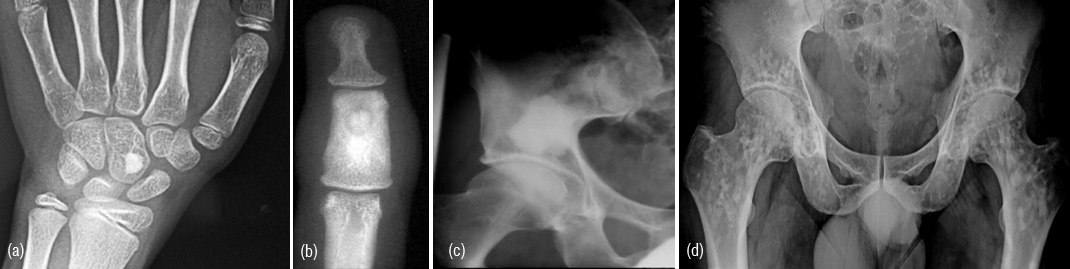

These are often encountered as circumscribed homogenous dense lesions on plain films. The size may range from few millimetres to a centimetre and may simulate osteoid osteoma which has typical radiological findings such as a nidus and surrounding reaction (Figure 1ab). It may grow and assume a large size when it is called a giant bone island (Figure 1c). Developmentally, these bone islands are cortical inclusions in trabecular bone. They may be multiple and involve many bones, and should not be mistaken for osteopoikilosis (Figure 1d).

Figures 1a,b,c,d: a) Bone island in capitate, b) Osteoid osteoma, c) Giant bone island in iliac bone, d) Osteopoikilosis.